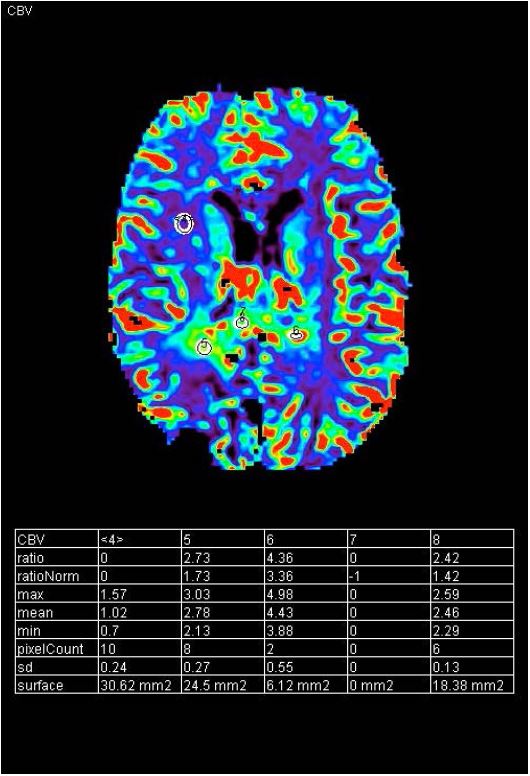

Під час DSC-перфузії спостерігалося збільшення об'єм мозкової крові (CBV) у місці ураження, що перетинає мозолисте тіло зліва (рис. 9). На MRS пік холіну був надзвичайно високим, було значно знижено Naa з Cho/Naa >>2. Також спостерігався невеликий пік лактату (рис. 7). Дані візуалізації були сумісні з рецидивом мультиформної гліобластоми, 4 ступеня за ВООЗ.

Рисунок 9 CBV lesion